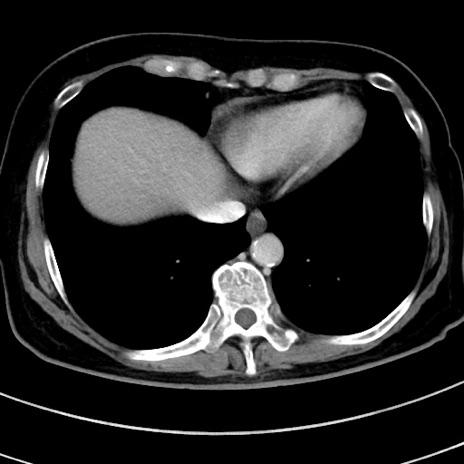

冠状断像

【症例】 60歳代女性

【主訴】むかつき、みぞおちの痛み

【現病歴】3日前よりむかつきがあり、食事がとれない。

【既往歴】糖尿病

【身体所見】発熱なし、心窩部圧痛軽度あるも、腹膜刺激症状なし。

【データ】WBC 7400、CRP 1.92